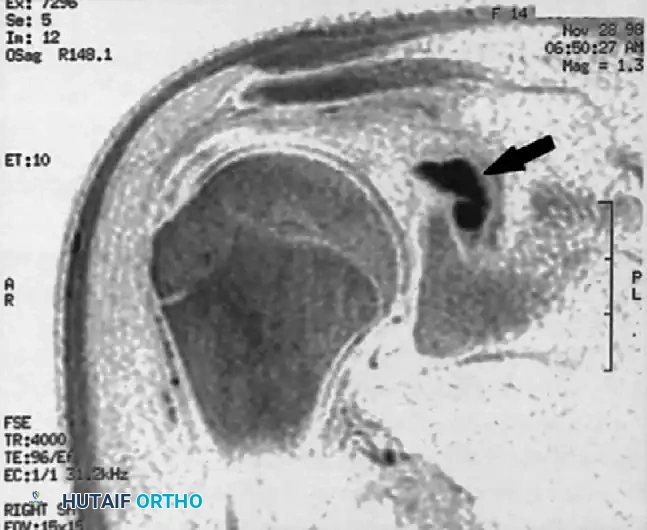

The following MR images demonstrate the classic presentation of a paralabral ganglion cyst causing entrapment neuropathy of the suprascapular nerve at the spinoglenoid notch:

FIGURE 46-16B: Sagittal/Coronal oblique MR image. The solid black arrow highlights a distinct ganglion cyst residing within the region of the spinoglenoid notch, exerting mass effect on the neurovascular bundle.